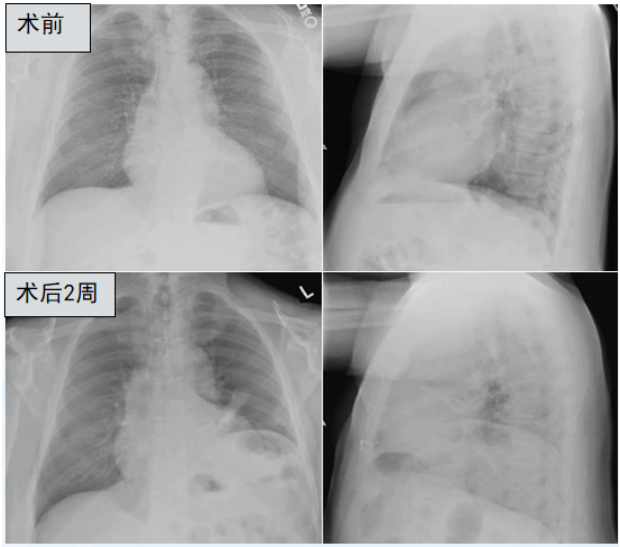

膈肌功能评估主要包括无创评估和有创评估。无创评估方法包括胸部影像学(胸部X线摄影、胸部CT、MRI)、肺功能、膈肌超声,有创评估方法包括压力测定(食道测压—跨膈压)、颤搐性跨膈压、膈肌肌电图。(1)胸部X线摄影:普通胸部X线摄影包括胸片与透视。胸片为静态检测手段,常用于单侧膈肌异常的诊断,如因肌纤维薄弱扩张所致的膈膨升、胸腹腔疾患所致的压力梯度异常或膈神经麻痹等。透视可动态评估膈肌的运动功能,是对胸片的进一步补充,并以观测膈肌运动幅度为主,但由于辐射及患者配合等问题在临床中并未广泛应用。图1为冠状动脉搭桥患者手术前后的胸片,术前胸片可见膈肌正常。术后2周患者出现呼吸困难,胸片可见左侧膈肌明显抬高,可能是由于术中损伤膈神经导致膈肌麻痹所致。(2)胸部CT:作为静态检测手段,胸部CT可以进行横断面扫描及三维重建,用于检测膈肌的器质性占位,三维重建能还原膈肌各部的立体结构,在残气量(RV)、功能残气量(FRC)、肺总量(TLC)等时相测量患者矢状位和冠状位的膈肌长度、表面积、膈穹隆、对合面积等,以此来量化膈肌的功能。图2所示为通过测量患者起病后第10天的膈肌宽度来估算膈肌的面积,结果发现膈肌面积缩小,提示存在膈肌萎缩及膈肌功能障碍。(3)胸部MRI/动态MRI:通过胸部MRI/动态MRI可以动态评估膈肌功能。如图3所示为正常人在TLC、FRC、RV三个体位时的膈肌形态,可以发现,从FRC到TLC时,膈肌明显下移。图4所示为对肌萎缩侧索硬化(ALS)患者膈肌进行的动态监测,在正常人在吸气和呼吸时,膈肌有明显的位移。但是ALS患者出现呼吸衰竭,无论是吸气还是呼气,膈肌位移都非常不明显,提示患者可能存在膈肌麻痹。